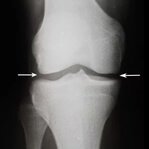

L'osteoartrite distrugge progressivamente il tessuto cartilagineo e porta alla deformazione dell'articolazione. Col tempo, anche i movimenti più semplici diventano impossibili e il dolore diventa costante. Una terapia adeguata aiuta a fermare la progressione della malattia.